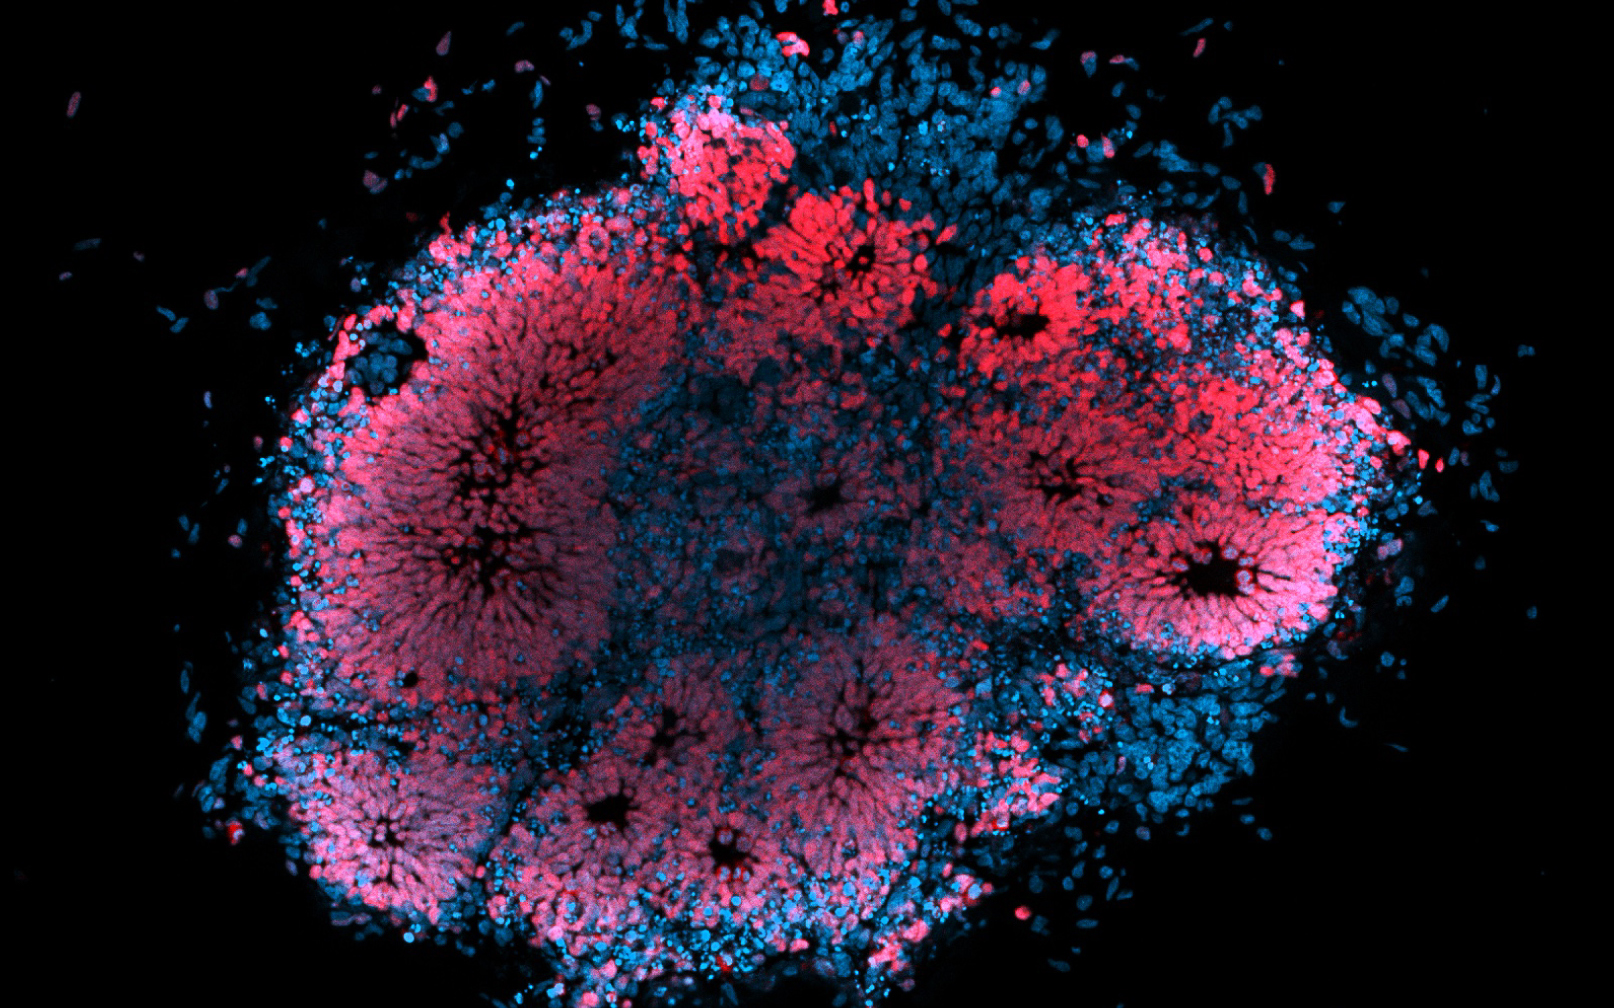

Microscopic image of human brain organoid infected with Zika virus. Image: Dr Julio Aguado (AIBN, UQ)

A University of Queensland-led project has used a ‘brain in a dish’ to study the effects of the Zika virus, taking research a step closer towards developing drugs to combat the infection.

“It’s a little like something out of a science fiction movie – we’re growing an artificial and microscopic human brain in a petri dish and testing the effect of the virus on its cells,” Dr Slonchak said.

“Stem cells self-organise into organ-like structures, or organoids, and in this case they have the structure and tissue architecture of the developing human brain.

“Our study shows the role of viral noncoding RNA in transplacental infection in pregnant mice and in cell death in human brain organoids.